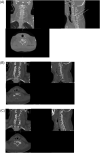

Missed cervical spine subluxation leading to bilateral facet dislocation with severe deformity requiring 360 fixation

A 41 year-old male that presented after a fall downstairs and the initial imaging was misinterpreted, missing a subtle abnormality, C5/6 subluxation. The patient presented later with neck pain and further imaging demonstrated bilateral facet dislocation with severe deformity requiring 360 spinal fixation.